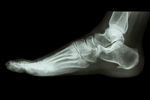

足底筋膜炎/足裏の痛み

【症例】足底筋膜炎

琴音さんの手術は、踵の骨を削る「内視鏡下骨棘切除術」と言う術式です。

手術を選択されますが痛みは変わらない訳ですから、「踵の棘が原因ではなかった」と言う結論になります。